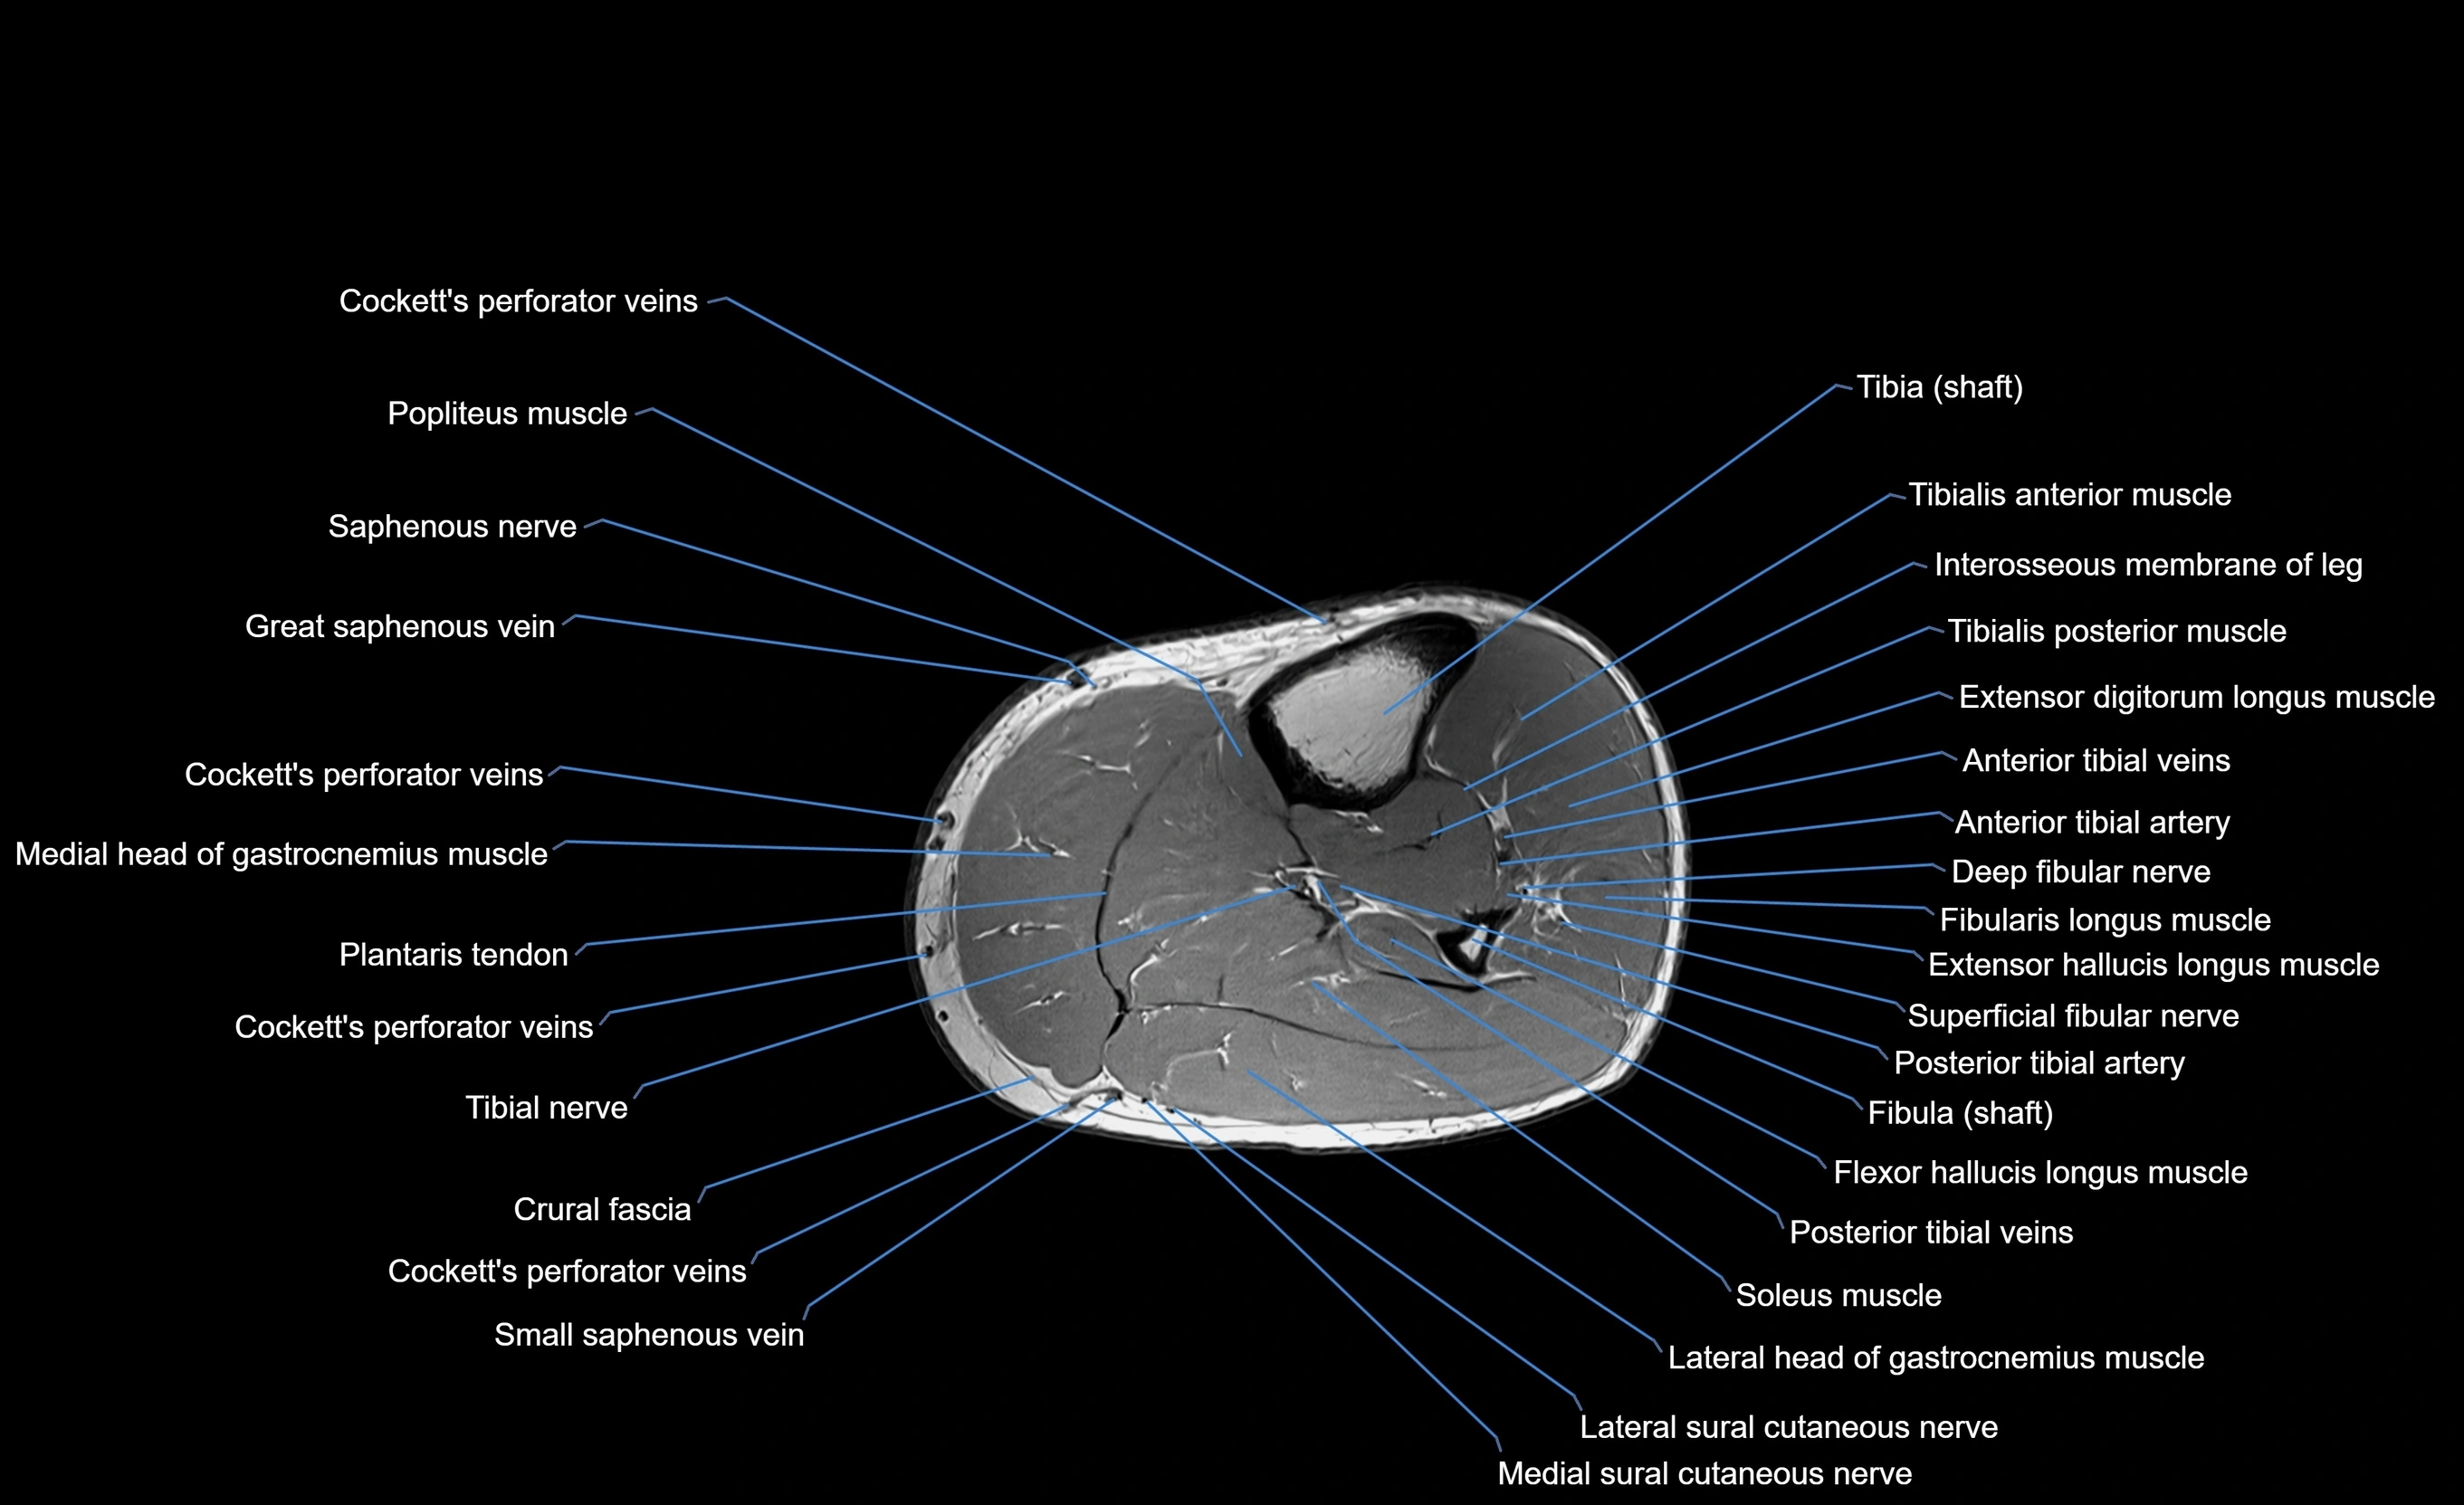

MRI image